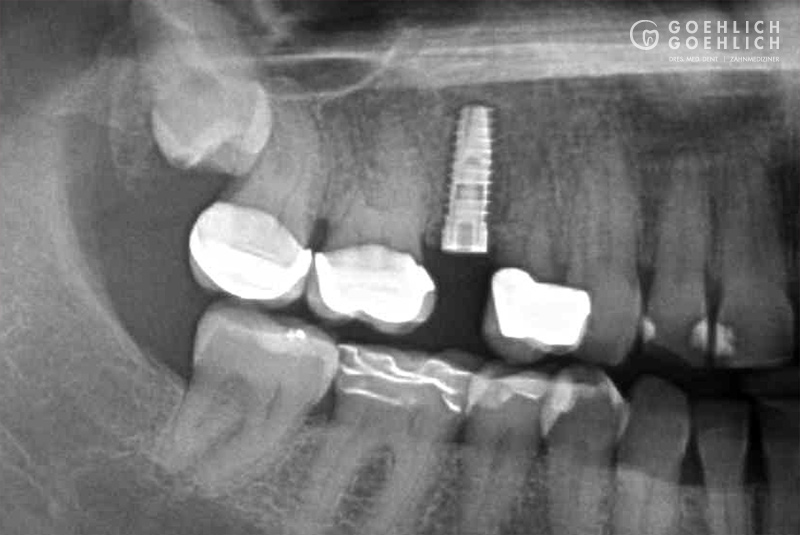

Mittels digitaler Volumentomographie (DVT) sind wir in der Lage, die knöcherne Ausgangslage vor Implantation dreidimensional darzustellen. So können die genauen Lagebeziehungen zu Nerven oder auch zur Kieferhöhle optimal bestimmt werden.

Als Implantat bezeichnet man in der Zahnmedizin eine künstliche Zahnwurzel, die nach Verlust eines eigenen Zahnes als Ersatz eingebracht wird. Das Implantat dient als Basis bzw. Verankerung einer festsitzenden Krone. Geht nur ein Zahn verloren, dient das Implantat zum Schluss der Lücke, ohne dass eine Brücke angefertigt werden muss und dafür die vielleicht intakten Nachbarzähne abgeschliffen werden. Damit schonen wir die umgebenden Zähne. Spätfolgen des Zahnverlustes, wie Kiefergelenkprobleme, Zahnwanderungen oder Karies können vermieden werden. Sind bereits mehrere Zähne verloren gegangen, die nur durch eine Teil- oder Vollprothese ersetzt werden können, ermöglichen wir durch das Einbringen mehrerer Implantate wieder einen festsitzenden Zahnersatz.

Implantate bestehen aus dem körperverträglichen und langlebigen Metall Titan. In einem minimalinvasiven operativen Eingriff setzen wir das Implantat in den Knochen ein. Die speziell bearbeitete Oberfläche garantiert ein zügiges Einheilen und das feste Verwachsen mit dem umgebenden Knochengewebe. Implantate können darüber hinaus den gefürchteten Knochenschwund in zahnlosen Kieferabschnitten verhindern oder verzögern. Den eigenen Zahnwurzeln ähnlich, übertragen Implantate die Kaukräfte auf den Kieferknochen. Dieser Trainingseffekt ist ein wichtiger Reiz für den Erhalt des Knochen- und Stützgewebes. Deshalb sollten Implantate möglichst bald nach dem Verlust oder Entfernen eines Zahns verankert werden.